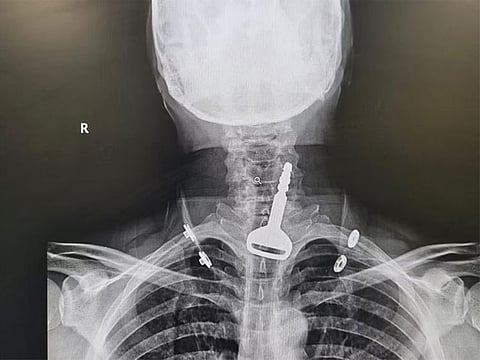

Cairo: A medical team at a Saudi hospital successfully performed a 15-minute endoscopic operation on a man and extracted a car key from his respiratory tract.

The man, aged 49, had been admitted into an emergency department at a hospital in Saudi Arabia’s coastal Al Qunfudah governorate suffering from a blockage in the airway.

Medical examinations showed a car key inside the respiratory passage. The man, a heart patient, had swallowed the key accidentally while playing with it.

He underwent an endoscopy and the key was extracted. He is staying at the hospital under medical observation until his health condition becomes stable.